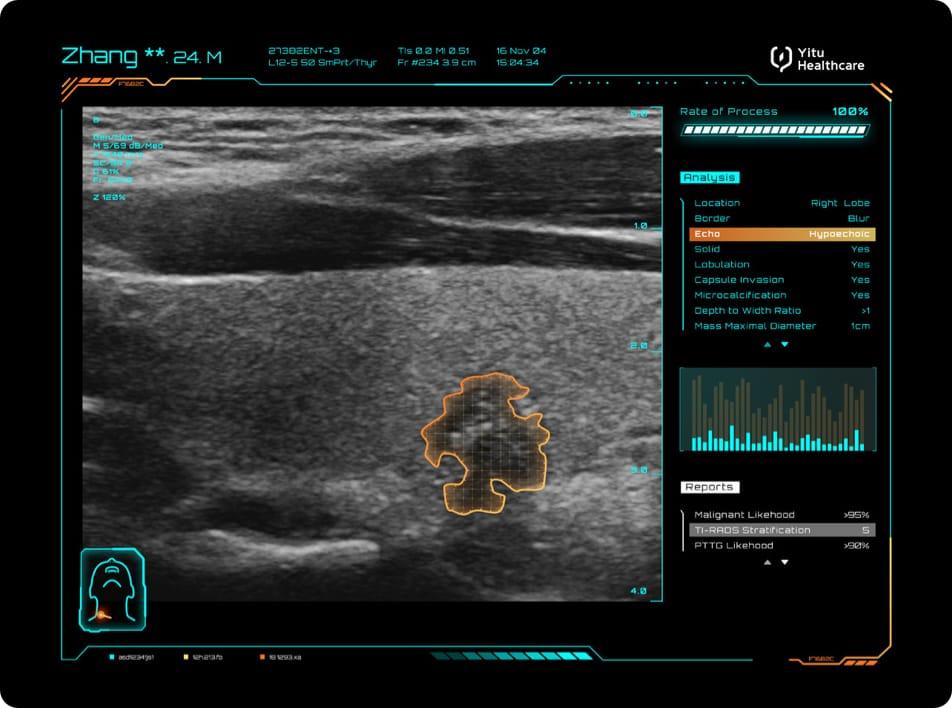

旗魚醫(yī)療聯(lián)合全國(guó)數(shù)百家一流醫(yī)療機(jī)構(gòu),以AI應(yīng)用提升醫(yī)療機(jī)構(gòu)服務(wù)供給能力,為高危癌種的早篩早診早治策略、科學(xué)研究及國(guó)家公共衛(wèi)生決策提供科學(xué)依據(jù),助力“健康中國(guó)2030”。旗魚“AI防癌地圖”會(huì)將醫(yī)療人工智能引入肺癌和乳腺癌等多個(gè)高發(fā)高危癌癥的篩查,減輕醫(yī)務(wù)人員工作負(fù)擔(dān),減少誤診漏診現(xiàn)象的發(fā)生,為大規(guī)模疾病早篩行動(dòng)的開(kāi)展提供有力技術(shù)支持,推動(dòng)中國(guó)腫瘤篩查進(jìn)入“AI+”時(shí)代。